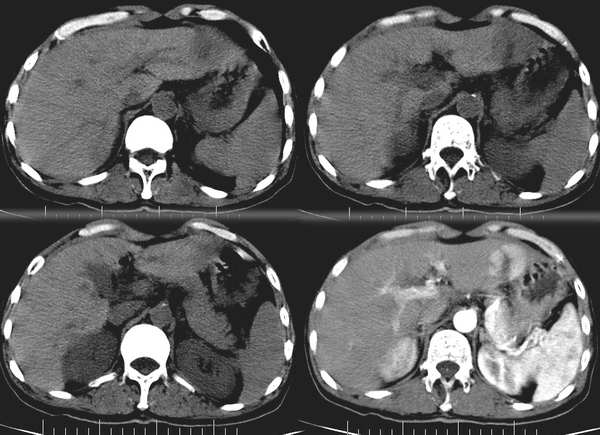

肝脏局灶性结节增生(fnh)。与肝癌鉴别点,病灶内有无强化的斑痕组织,该病例有此特点。

增强扫描病灶中央见裂隙状低密度影,支持局灶性结节状增生[emb6]

fnh:动脉期明显强化,静脉期呈等密度,平衡期呈低密度.应该算是典型表现.

支持肝癌诊断,fnh在门脉期应该与肝脏呈等密度。建议mri检查。

病灶边缘环形增强,提示纤维包膜形成,符合肝细胞癌纤维板层型,只是未见钙化,与局灶性结节状增生实在是不好鉴别.期待病理结果.